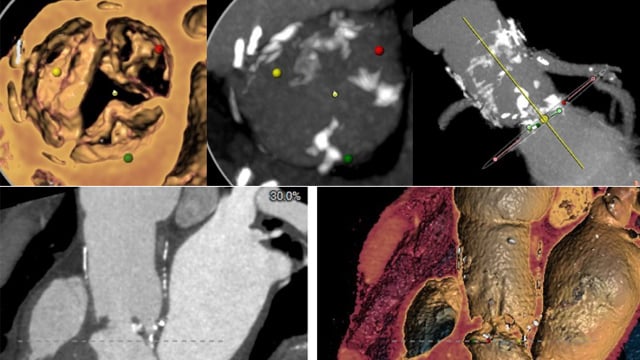

TAVI: complex vascular access

17 Nov 2025 – From PCR London Valves 2025

This session addresses the challenges of complex vascular access in transcatheter aortic valve implantation (TAVI). It discusses strategies for navigating difficult thoraco-abdominal aortic anatomies, managing double aortic arches, and overcoming hostile femoral access. Case studies illustrate meticulous planning and innovative solutions essential for successful TAVI in...

TAVI: challenging anatomies

17 Nov 2025 – From PCR London Valves 2025

This session explores the management of challenging anatomical conditions in TAVI procedures. Topics include strategies for difficult self-expandable valve delivery angles, addressing complications occurring during and after TAVI, and approaches for patients with severe kyphosis or complex structural abnormalities such as aneurysms and septal anomalies.